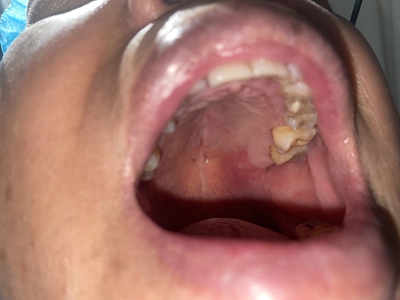

口腔溃疡又称复发性口疮,是慢性的口腔黏膜小溃疡,深浅不等,为圆形或椭圆形损害,可反复和周期性复发。多发生于口腔非角化区,如唇黏膜、舌头等处,预后较好,可自行痊愈。

口腔溃疡为圆形或椭圆形,直径0.2-0.5cm,溃疡单个或由数个连成一片,溃疡表浅边缘整齐,外观呈灰黄色或灰白色,上覆盖黄白渗出膜,周围黏膜充血、水肿而有红晕。

皮损局部有烧灼样疼痛,于进餐时加重,影响进食、说话。严重溃疡直径可达1-3cm,深及黏膜下层甚至肌肉。